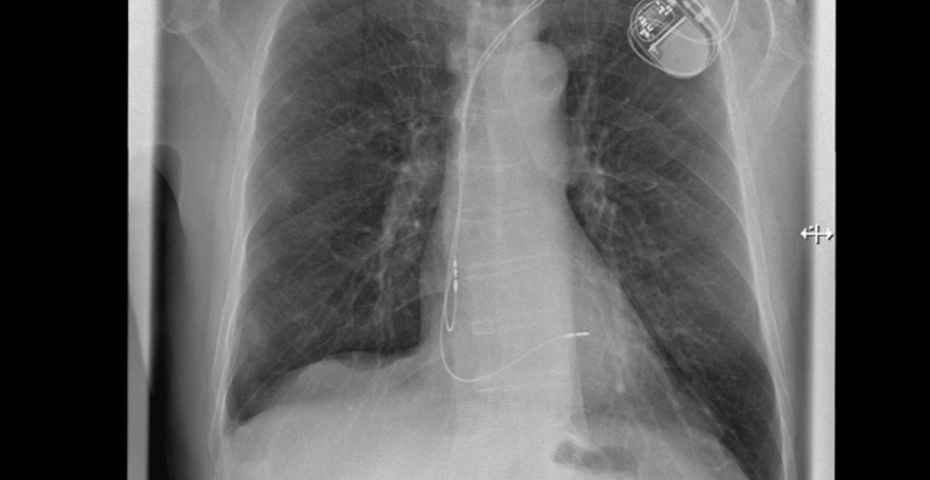

Für diese Patienten kommt eine minimalinvasive Herzklappenintervention infrage. Dabei ist keine Herzoperation mit Verwendung einer Herz-Lungen-Maschine notwendig. Stattdessen findet der Eingriff mittels Katheter über die Leistenvene statt. Über den Katheter, einen dünnen Kunststoffschlauch, wird ein Clip zum Herzen geführt. Dabei können die Segel der Mitralklappe mit einem MitraClip bzw. der Trikuspidalklappe mit einem TriClip gefasst und geclippt werden. Dadurch halten die Segel wieder zusammen und die Undichtigkeit der Klappen wird deutlich reduziert. Während der Untersuchung wird unter Narkose eine kontinuierliche Überwachung mit Ultraschall, einer transösophagealen Echokardiographie, durchgeführt. Dadurch können die Clips jederzeit geortet und optimal platziert werden.

Moderne Klappenreparatur in der Kardiologie mit MitraClip und TriClip

Das Eingriffsrisiko bei der Implantation eines MitraClip oder TriClip ist deutlich geringer als bei einer Operation. Ob das Verfahren individuell infrage kommt, muss von einem Heart Team, bestehend aus Fachärzten der Kardiologie, Herzchirurgie und Anästhesie, beurteilt werden. „In der Kardiologie des Diakonie Klinikums Jung-Stilling in Siegen wird diese moderne Methode zur Herzklappenreparatur regelmäßig und mit Erfolg angewandt. Dadurch sind wir nicht nur in der Region Siegen, sondern auch rund um Köln/Bonn, Bochum, Dortmund und in Hessen bereits als kompetenter Ansprechpartner bekannt und eine überregionale Anlaufstelle für viele Herzpatienten“, betont Prof. Dr. Dursun Gündüz, Chefarzt der Kardiologie am Diakonie Klinikum Jung-Stilling in Siegen.